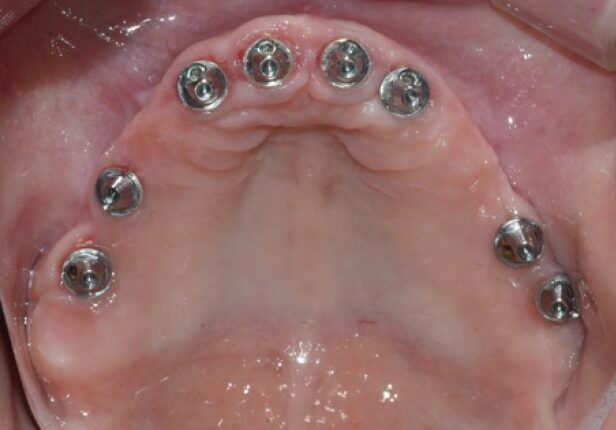

Mandibular Full case

Implant placement

AXA positioning